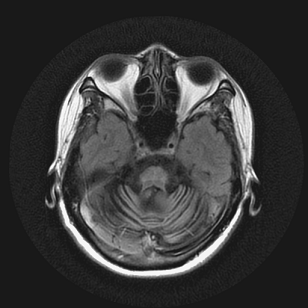

【112-1 醫學(四) 第51題】59歲男性因為姿勢性低血壓暈倒多次,他同時還有動作遲緩、步態不穩及性功能障礙問題,他的腦部磁振造影掃描結果如下圖,下列何者為最可能的診斷?